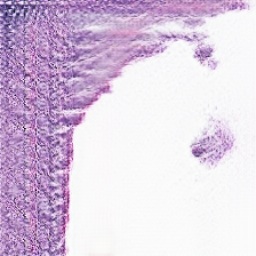

The Figure 3 shows virtual H&E generation from light-sheet microscopy image. Each column represents a different type of image. Each row corresponds to a different slice. From these images, it can be observed that the CycleGAN has learned to map the nuclear and cytoplasmic signals to the characteristic H&E colors. Overall tissue morphology and structure are largely preserved, demonstrating that the model captures the spatial relationships of nuclei and cytoplasm from the fluorescence channels.

The Figure 4 illustrates how CycleGAN outputs evolve across training epochs. Each column shows the virtual H&E image generated at a specific epoch, while each row corresponds to the same slices. Early in training, the images may exhibit incomplete or uneven staining and less clear tissue structure.

As training progresses, the representation of H&E changes slightly and becomes visually more consistent. However, through comparison across epochs, it can also be observed that the CycleGAN generated results exhibit certain drawbacks, including variability in staining intensity, occasional loss of fine structural details, and the introduction of artificial texture patterns that are not present in the original fluorescence images. Due to the lack of ground truth H&E images, the quality of the generated virtual H&E cannot be quantitatively validated in this study and is assessed primarily through visual inspection. If paired ground truth H&E data were available, quantitative performance metrics such as cell count agreement or dice score and intersection of union (IOU) of the stained cells (positive cells) in the virtually generated image with respect to the real image [2].

| C01 | C02 | virtual H&E images |

|---|---|---|